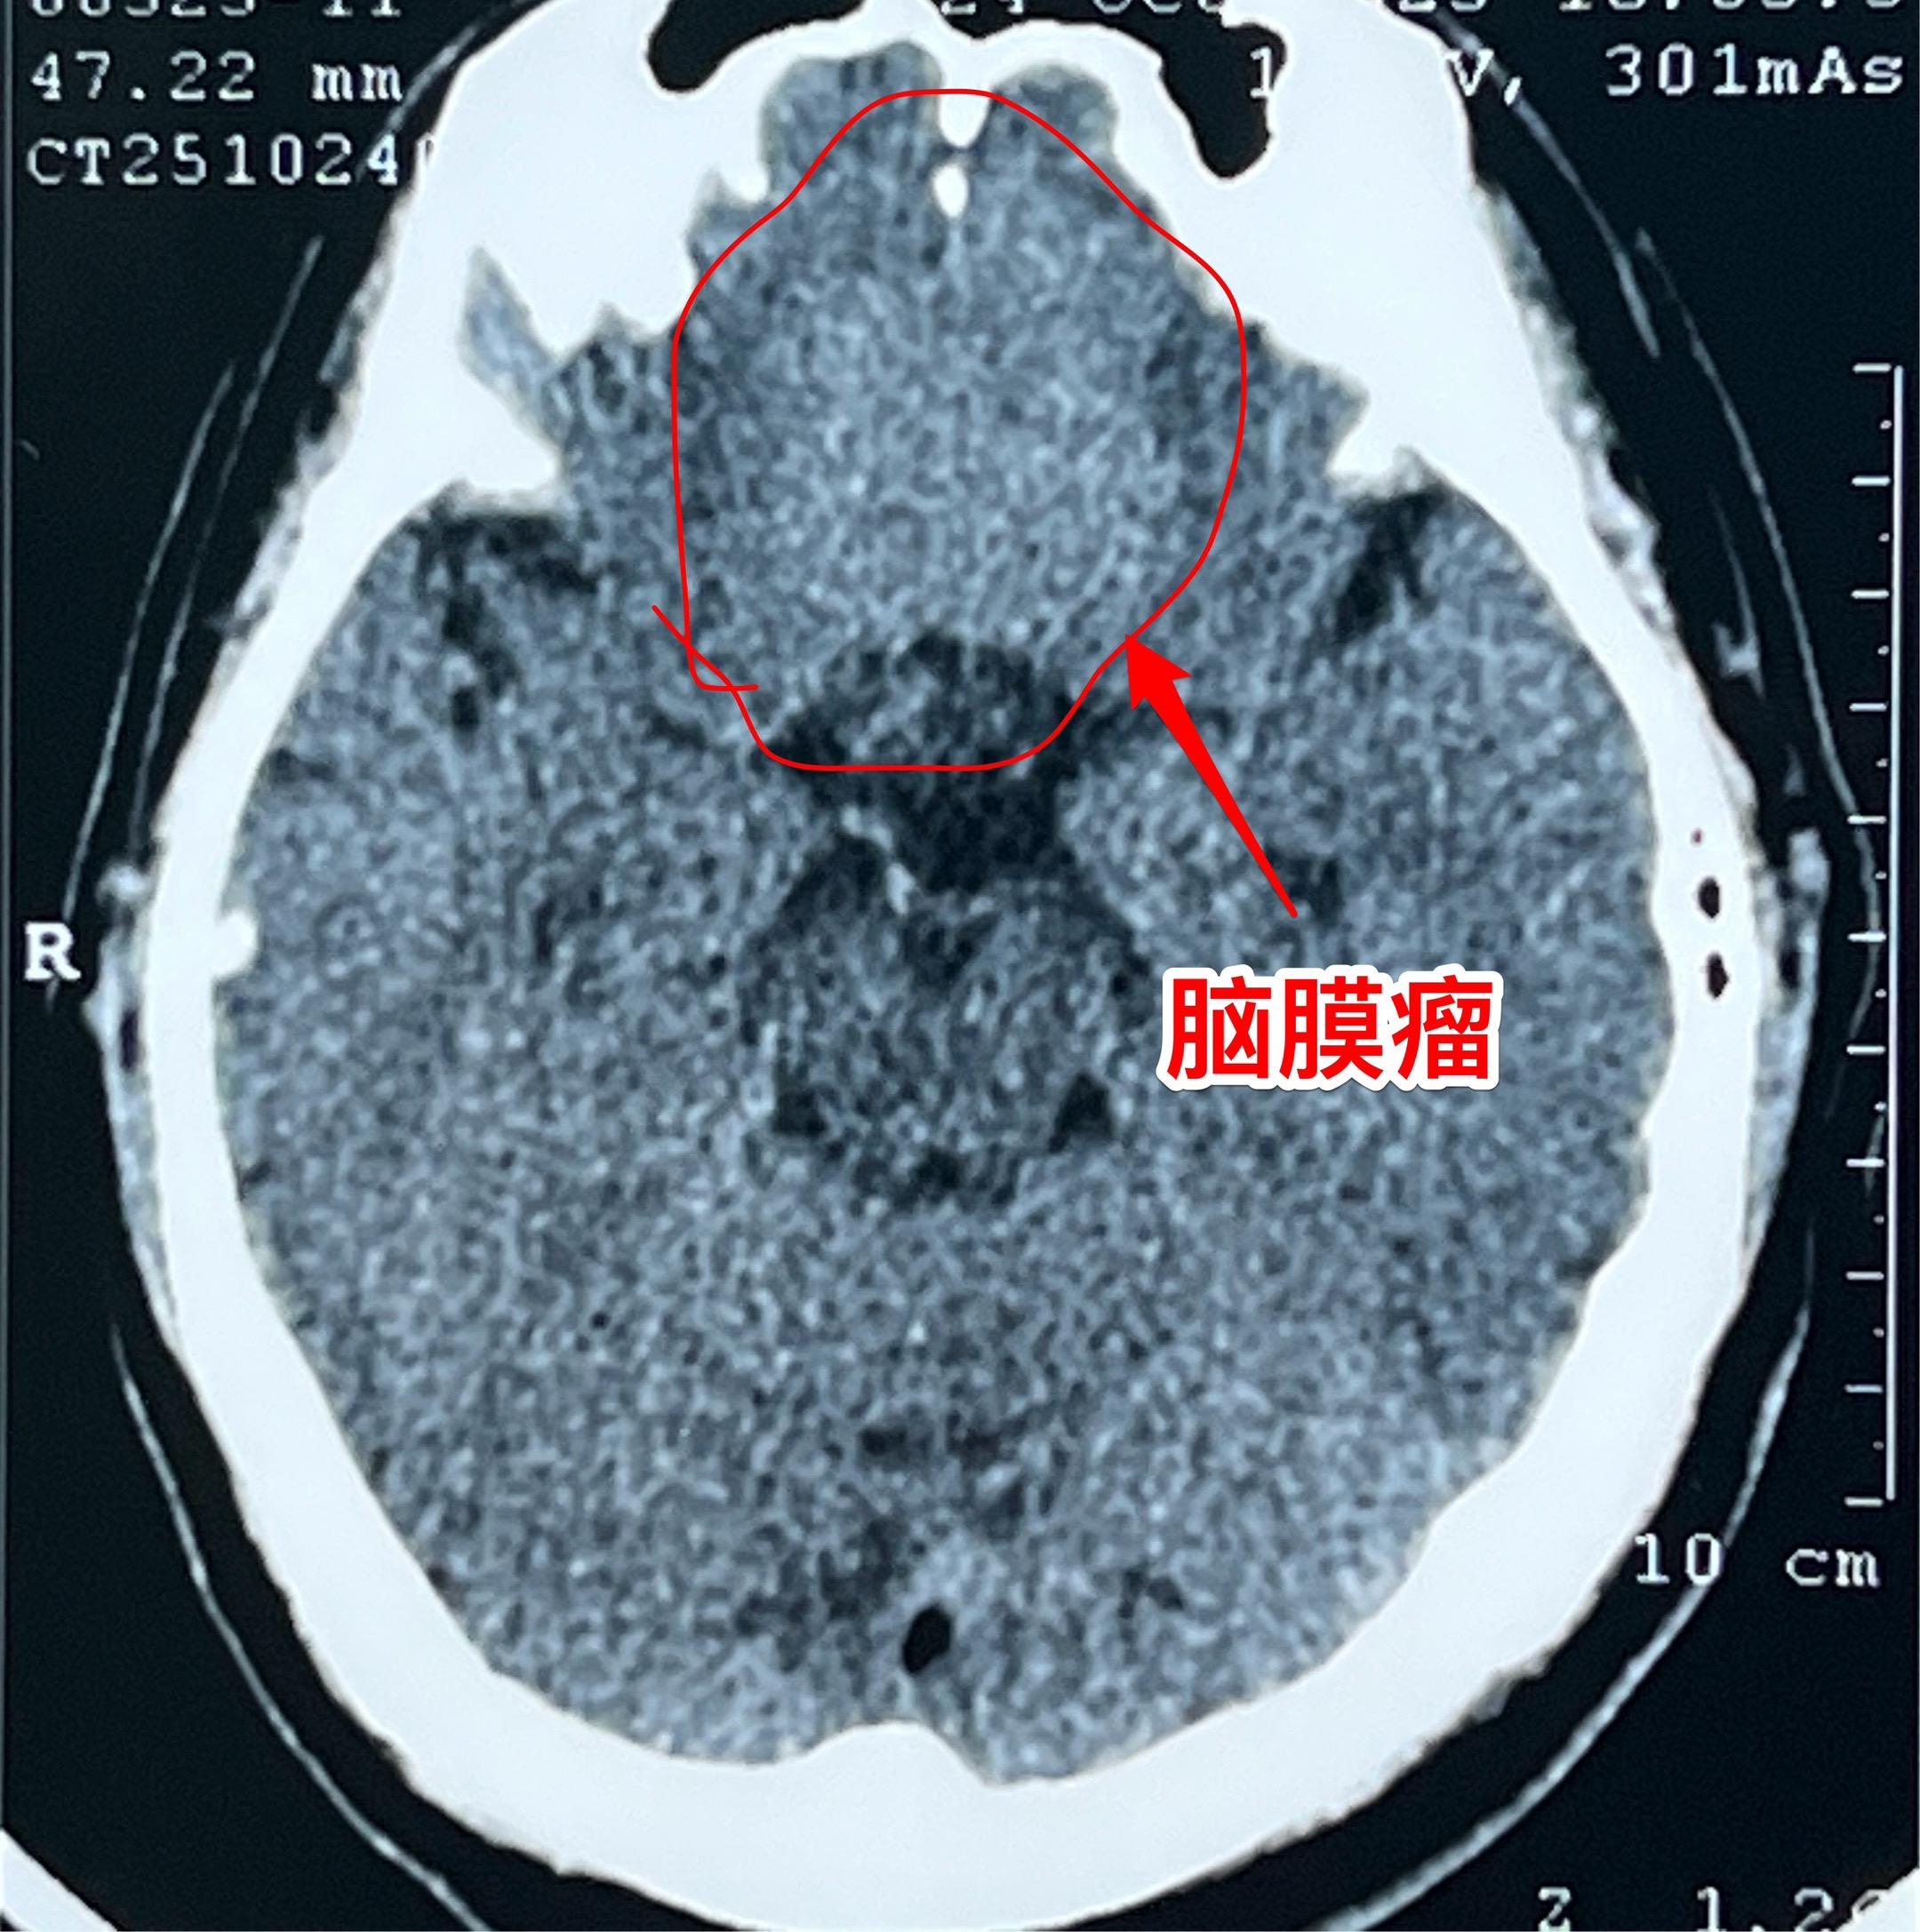

颅底脑膜瘤,彻底切除是首选治疗。59岁男性,体检发现这个肿瘤,无头痛症状,无视力下降,怀疑是脑膜瘤。 2025年10月30日作了手术,术中证实是脑膜瘤,肿瘤有完整包膜。彻底切除,争取治愈。